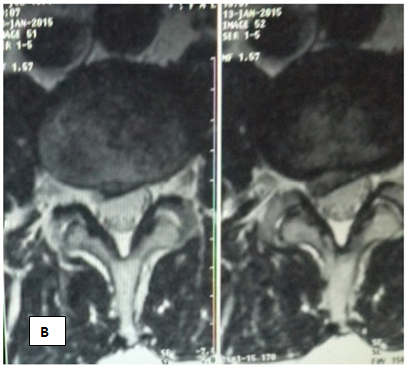

Clinical examples

Sick F, 44 years old, n stumble In February 2015, after months of unsuccessful treatment by a neurologist with complaints of acute pain, radiating to the right n izhnyuyu limb. He notes periodic weakness in his right leg, a limp. When examining antalgic scoliosis to the left, the relative shortening of the right leg. With th Lassega right 15 degrees, VAS 7-8 points. MRI of predelyaetsya dorsal sided medial-paramedian disc herniation L3/L4, with a tendency to sequestration of up to 0.8 cm, extending to the right intervertebral foramen, with its contraction, having caudal spread sequestering component along the body of L4 vertebra to 0.5cm in the right lateral pocket, with compression of the right nerve root, compressing adjacent sections of the dural sac (Figures 1A & 1B).

Figure 1 Patient F. MRI examination before treatment.